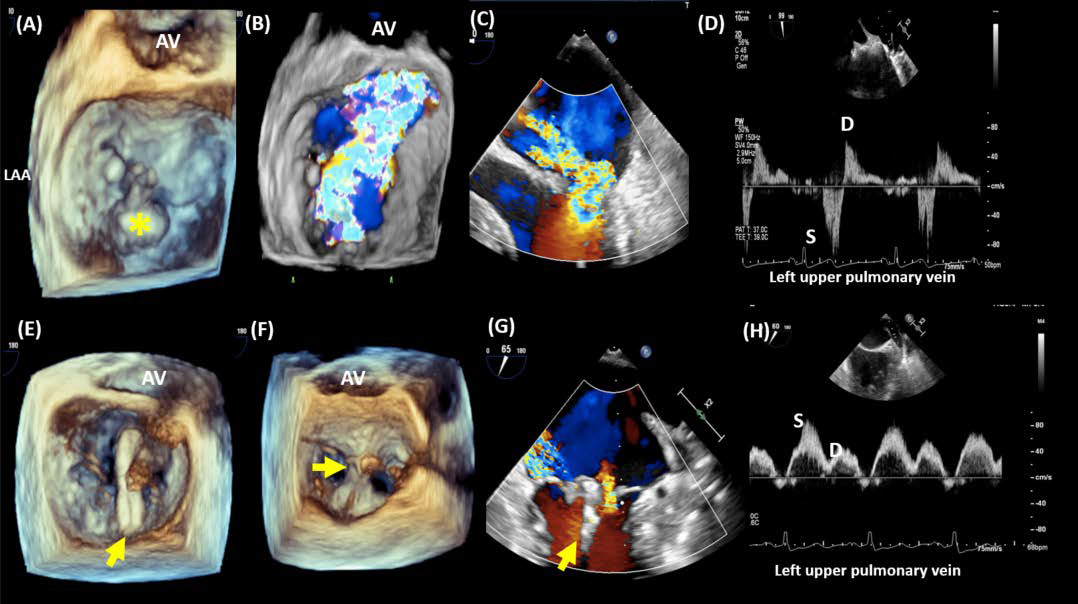

Fig. 4 demonstrates successful TEER of the mitral valve in a patient with P2 leaflet flail.

Fig. 4.Transcatheter edge-to-edge repair of a case of a flail posterior leaflet. 3-dimensional imaging (A) demonstrates a flail P2 (*) with significant anteriorly directed MR (B). 2-dimensional baseline TEE imaging demonstrates the flail posterior leaflet with severe anteriorly directed MR (C). Left upper pulmonary venous flow at baseline shows systolic flow reversal, indicative of severe MR (D). The MitraClip device (arrow) is advanced into the left atrium and positioned perpendicular to the line of coaptation of A2-P2 (E). The device is then advanced into the LV and deployed to approximate the A2-P2 leaflets, resulting in a tissue bridge (F). This results in significant reduction in MR (G) with dominant systolic flow in the left upper pulmonary venous flow (H). AV, aortic valve; LAA, left atrial appendage.